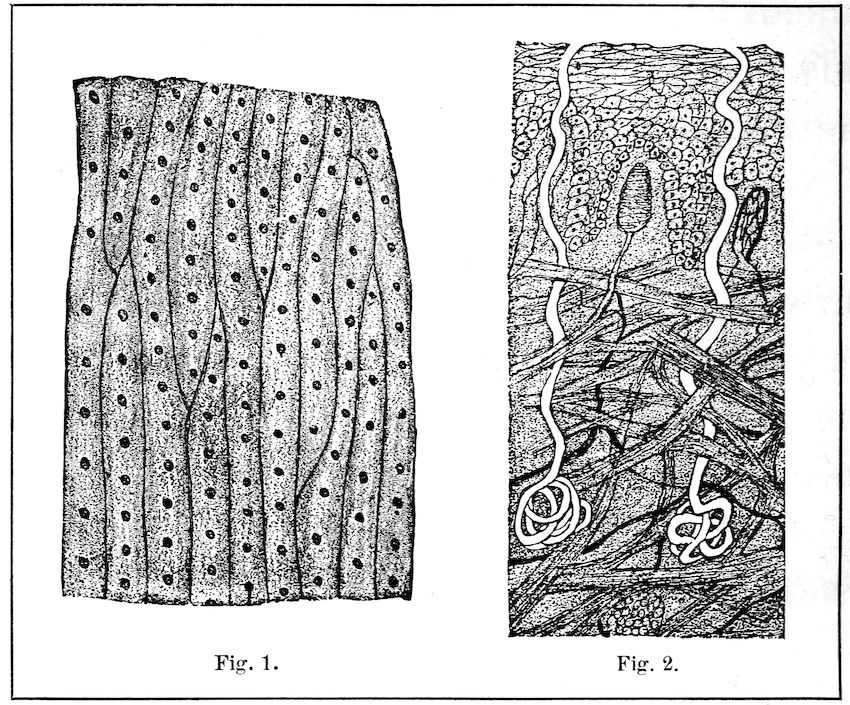

Besides the outer garments in which we clothe it, the body has a garment of its own. This garment is never laid aside; and though it is in constant use, it never wears out. We call it the skin. The skin is meant to protect the body. Lying close under it are many nerve ends, delicate blood vessels, oil glands, sweat glands, and other tiny organs that are too small to be seen without a microscope, but which are needed to keep the 66body in good order. In the pictures which are shown on this page, you will see how these tiny organs look when they are many times magnified.

The Skin Magnified

Fig. 1. Surface showing openings of pores.

Fig. 2. Side view of sweat glands and pores.

Now, like our outer clothing, this garment of the body needs to be kept very clean. You know that in this country when we take exercise, or, during the heat of the day, even without our taking exercise, the surface 67of the skin gets moist, little drops of water stand on it, and even run down our faces or make our hands wet. We call this moisture perspiration, and say that we are sweating or perspiring with the heat. The drops of water come from openings in the skin, which we call pores. These are little tubes connecting with sweat glands below the skin. You will see in the picture how these sweat glands look, and how the pores come to the surface.

The perspiration is not pure, clean water; it contains many impurities which the lungs, kidneys, and other organs have not cast out from the body. It is the work of the skin to help carry off these impurities, and it does this by means of sweat glands and pores. If the perspiration dries on the skin, the impurities remain; they stop up the pores and make the body unhealthy. It is to prevent all this that we bathe often. Bathing keeps the pores of the skin open and the skin itself in a healthy condition. We use soap because the skin secretes oil as well as 68perspiration. This oil is to keep it soft and smooth, but it is needful that the excess of it should be washed off with soap, in order that the oil glands may not become clogged.